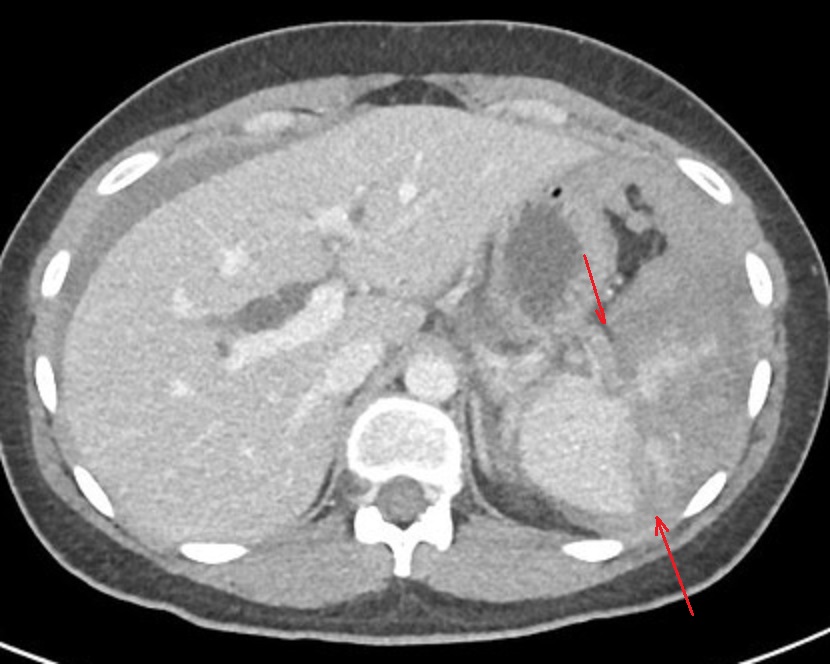

Image radiologique TDM d'un

traumatisme de la rate a grade IV avec aspect

radiologique de hematome itraparenchymeteuse marque

, dechirude capsulaire et de devascularisation de

bord anterieur . Coupe axiale TDM avec contrast

intraveineuse phase veineuse . |

Image rasdiologique d'une traumatisme de

la rate avec lesions hematome intraparenchymeteux

diffuse et dechirure de bord anterieure avec

devascularisation de artere splenique ( grade V ) .

Coupe TDM axiale phase veineuse |